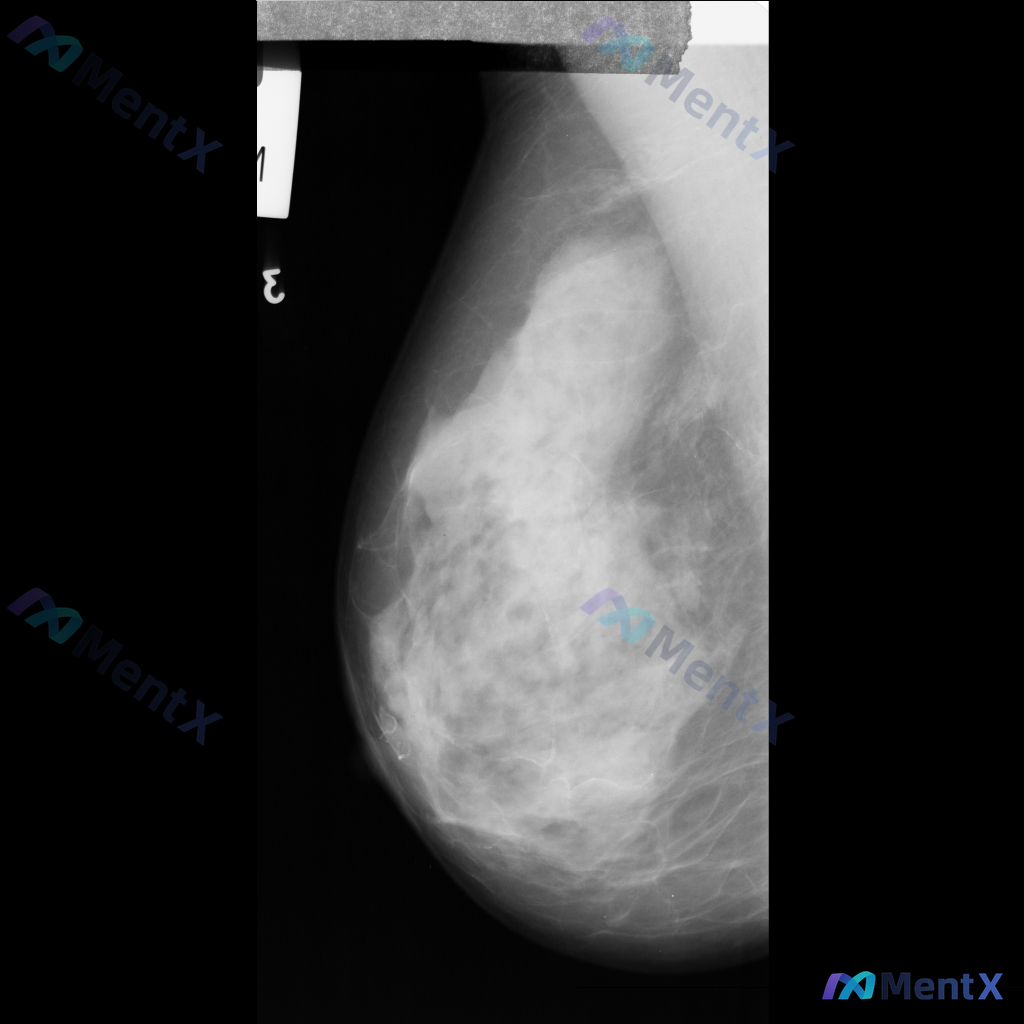

整理到一份右侧乳腺内外斜位钼靶X光片的影像资料,大家可以一起讨论下: - 影像中可见散在的纤维腺体密度,密度较高 - 发现多发斑点状或细小钙化点,分布散在,目前倾向良性特征 - 另有局部模糊的不对称致密影,与背景腺体组织融合,未见明确毛刺或结构扭曲等恶性特征 单看这份影像描述,大家会优先考虑什么方向...

整理到一张乳腺钼靶片的读片资料,想和大家讨论下判断方向。 基本情况: - 影像:右侧乳腺内外斜位(MLO)钼靶 - 背景:致密型乳腺(多量腺体型/不均匀致密) 异常表现: 1. 右乳中上象限可见一局限性不对称致密影,形态不规则,边界部分模糊,与周围腺体融合 2. 该区域周围可见可疑结构扭曲,小梁结构...

整理到一份乳腺钼靶的影像描述资料,想和大家讨论一下读片思路。 基本情况: - 图像显示为不均匀致密型乳腺 - 主要异常:乳腺中部区域可见片状致密影,与周围腺体组织相融合,边界不清晰 - 目前仅为单侧乳腺图像,无法进行双侧对比 - 影像中未发现明确的边界清晰或不规则形态肿块、可疑钙化、结构扭曲、皮肤增...